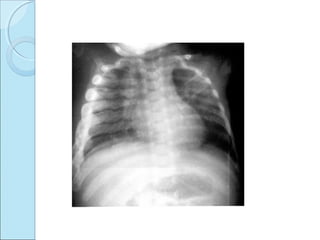

CAFFEY’S DISEASECAFFEY’S DISEASE

 INFANTILE CORTICAL HYPEROSTOSIS.

SITESSITES

 Mandible.

 Ribs.

 Clavicle.

 Scapulae.

 No spine involvement.

 Diapysis involvement.

RADIOGRAPHIC FEATURESRADIOGRAPHIC FEATURES

 Marked periosteal proliferation.

 Cortical thickening.

 Soft tissue swelling.

OUTCOMEOUTCOME

 Bone returns to normal by 12 weeks.

Osteoblastic periosteal lesion involving shaft of ulna

,also lateral aspect of radius.

Deformity, periosteal reaction. Soft tissue

swelling.